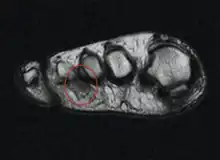

Though a neuroma is a soft-tissue abnormality and will not be visualized by standard radiographs, the first step in the assessment of forefoot pain is an X-ray to detect the presence of arthritis and exclude stress fractures/reactions and focal bone lesions, which may mimic the symptoms of a neuroma. Ultrasound (sonography) accurately demonstrates thickening of the interdigital nerve within the web space of greater than 3mm, diagnostic of a Morton’s neuroma. This typically occurs at the level of the intermetatarsal ligament. Frequently, intermetatarsal bursitis coexists with the diagnosis. MRI can distinguish conditions that mimic the symptoms of Morton's neuroma, but when more than one abnormality exists, ultrasound has the added advantage of determining the precise source of the patient’s pain by applying direct pressure with the probe. Ultrasound may also be used to guide treatment such as cortisone injections into the webspace, as well as alcohol ablation of the nerve.

Microscopically, the affected nerve is markedly distorted, with extensive concentric perineural fibrosis. The arterioles are thickened and occlusion by thrombi are occasionally present.[13][14]